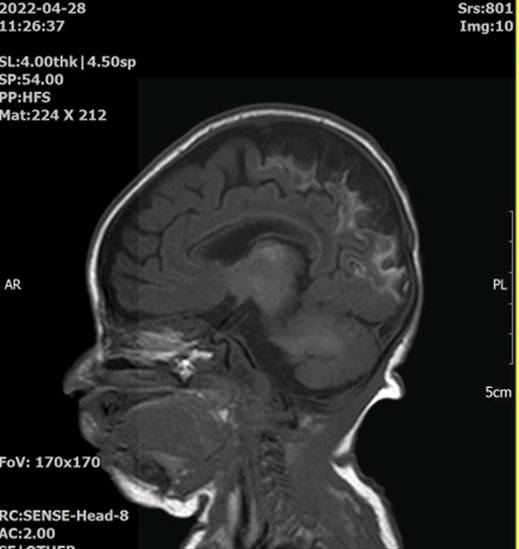

김양은 뇌손상에 따른 인지장애, 언어장애 등 발달 장애를 갖게 됐다. 뇌에 산소 공급이 중단되며 대뇌피질이 거의 소실됐다. 현재 39개월인 김양은 혼자 일어서거나 걷기 힘들고, ‘엄마·아빠’ 등 10여개 단어만 말할 수 있다. 손가락이 안으로 말려 혼자 밥을 먹는 등 일상적인 동작 수행도 도움이 필요하다. 최씨는 매일 오전 아이를 데리고 재활병원에 가서 걷기 훈련 등 재활치료를 받게 하고 있다.